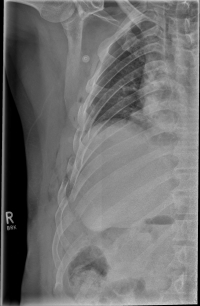

Rib Fractures

The rib fracture is a common injury to the chest. It occurs frequently in (car) accidents, falls during cycling and contact sports. Due to their anatomical position, especially the 4th - 9th ribs are affected.

As a rule, the rib fracture is diagnosed by X-ray. In severe cases or ambiguous X-ray findings, a layer imaging, for example computer tomography (CT), can also be performed.